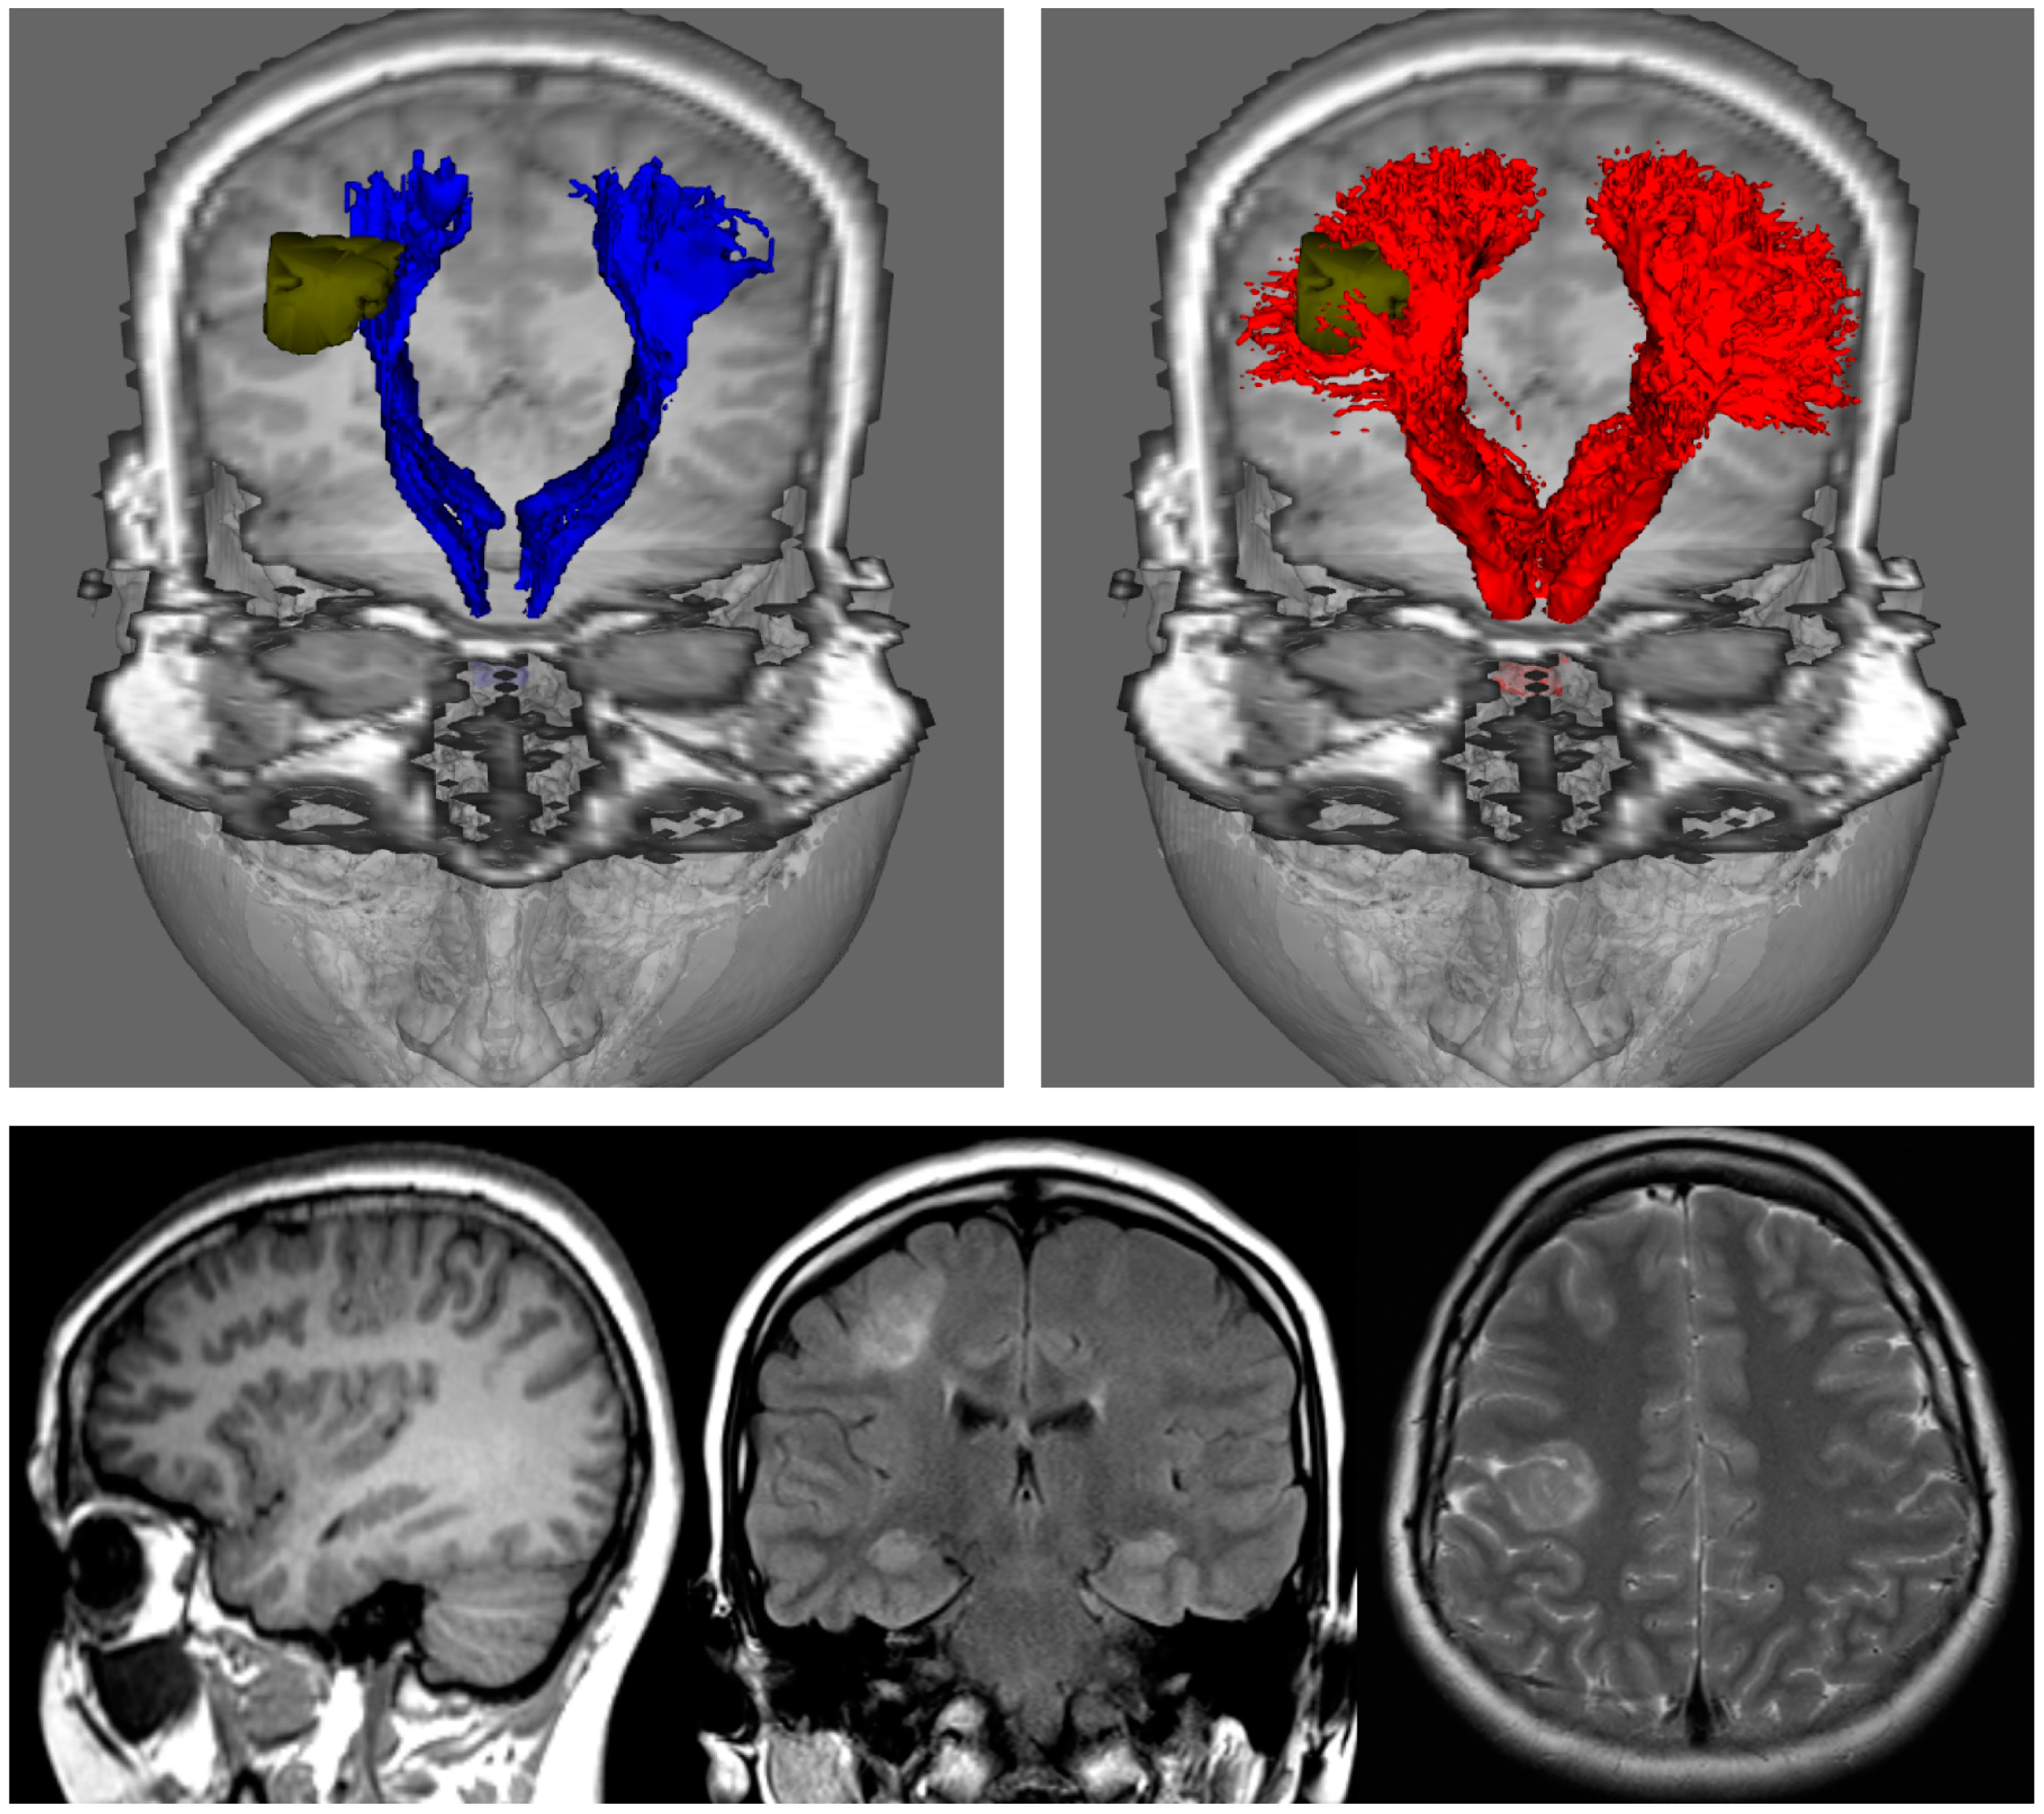

Figure 3.

Fibre-tracking results on a 24-year-old woman with a right focal cortical dysplasia situated in the right posterior frontal lobe (see images in bottom row). These results were obtained using a seed region in the brainstem and target regions in the sensorimotor cortices. DTI-based tractography (blue) and CSD-based tractography (red) were derived from the same diffusion MRI data set); segmented pathology volumes (green) overlaid on T1-weighted image. DTI-based tractography suggests that only the medial aspect of the lesion impinges on the corticospinal tracts, whereas CSD-based tractography suggests that the lesion is enveloped by medial and lateral projections. DTI: Diffusion Tensor Imaging; CSD: constrained spherical deconvolution. Note that while only DTI combined with deterministic tracking is shown in the top-left image, the results of combining DTI with probabilistic tracking are expected to be very similar (cf. left and middle images in Figure 2). Figure modified from a figure previously published in [30], with permission of American Association of Neurological Surgeons, 2013.